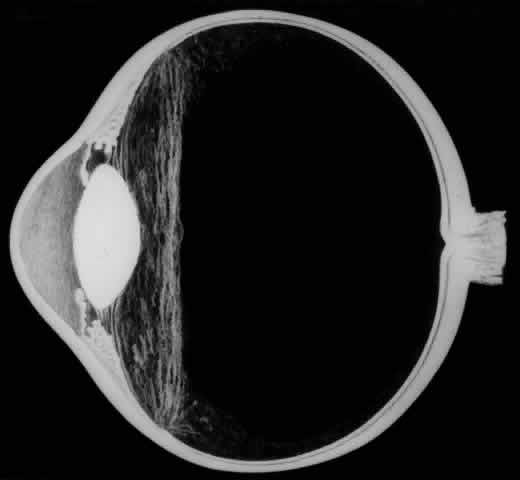

The outer surface of the inverted retinal flap (Fig. 1) should be examined for signs of epiretinal tissue proliferation, which may produce radial or star-shaped folds in the flap. Vitreous base traction produces detachment of the anterior edge of the giant tear and the pars plana epithelium anterior to it in 82% of giant retinal tears.9 It is important to identify and treat detachment of the pars plana epithelium that extends beyond the ends of the giant tear because leakage of subretinal fluid beneath it can be a potential source of postoperative posterior retinal detachment.

Fig. 1. Superior giant retinal tear extending from 9:30 to 3:30 meridian. The retina is torn at the posterior border of the vitreous base. Posterior retinal flap is invertd over the optic disc. Anterior edges of giant tear, ora serrata, and pars plana are detached from the 9:30 to 3:00 meridians as a result of vitreous base traction.